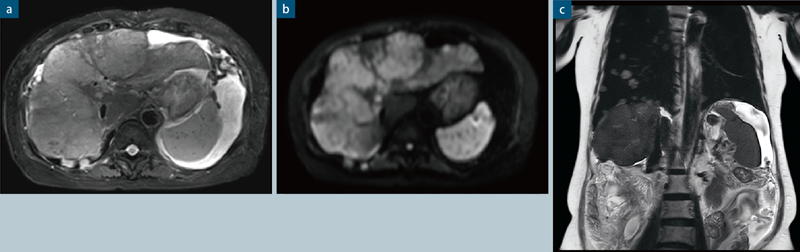

●症例6 転移性肺がん,転移性肝がん

30エレメントコイルで誘電パッドを用いずに撮像することで,効率的かつ快適な検査を行っている。アキシャル像(T2, diffusionとも)ではPACE法による呼吸同期,コロナル像では同期なしの安静呼吸下検査で患者負担を軽減している。

a: TSE,BLADE,SPAIR,TR/TE:3562/73,スライス厚5mm,マトリックス:256×256,iPAT facotr:3,撮像時間:54秒

b:diffusion,PACE,TR/TE:6573/54,スライス厚5mm,マトリックス:85×128,b-value: 1000,iPAT facotr:2, 撮像時間:2分30秒(b-value:150,500,1000)

c: HASTE,TR/TE:1300/146,スライス厚5mm,マトリックス:320×320,iPAT facotr:2,撮像時間:0.65秒/1slice